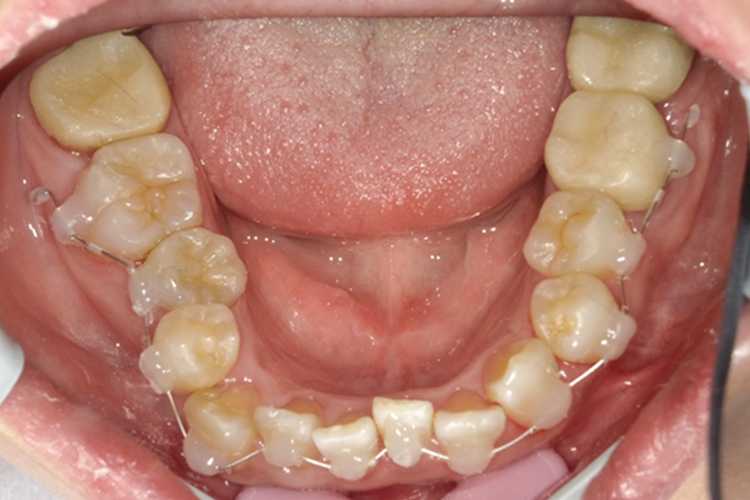

下顎拡大装置

| 費用 | 77,000円 |

|---|---|

| 治療期間 | 約3ヶ月~6ヶ月 |